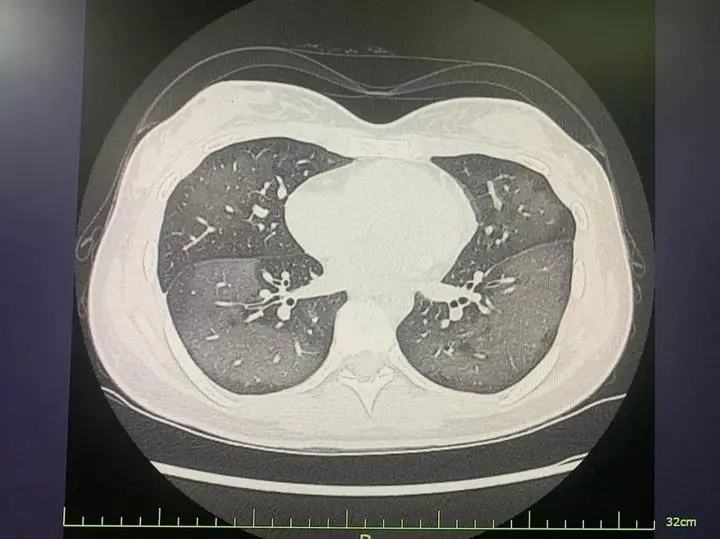

经CT检查发现,丽丽的双肺呈现大范围白色样病变,报告提示“白肺”。

患者肺部CT

医生解释,此类“白肺”与使用防晒喷雾时吸入的有害物质有关,喷雾中的某些化学成分会刺激诱发一系列过敏反应,从而导致广泛的气管、支气管乃至肺水肿,让肺部无法正常工作。